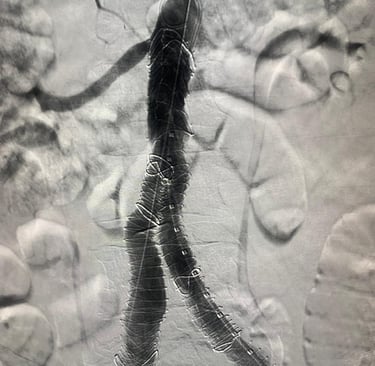

Galería

Imágenes de nuestros tratamientos en angiología y cirugía vascular.